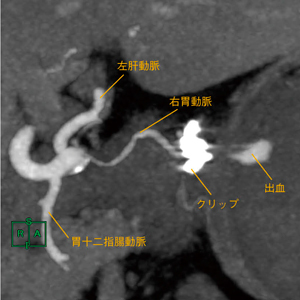

slab MIP作成の実際の手順は,画像を読み込んでMIP表示に切り替え,スライス厚とスライス間隔を調整するだけの単純なものである。しかし,MIPの表示法や表示厚,観察部位の角度は,医師と十分に相談しながら設定する必要がある。医師と相談の上,画像処理を行った結果,図2に示すように横断像だけでは観察困難な血管の把握や,出血源へのアプローチルートの確認,周囲血管との関連が明瞭な画像作成ができた。

図2 slab MIP最大値表示

5mm厚としたことで,主要血管との関係や右胃動脈の変異,クリップから出血源までが明瞭に分離して表示できている